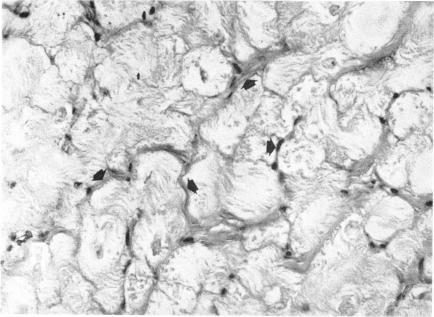

Cardiac innervation: anatomic and pharmacologic relations.